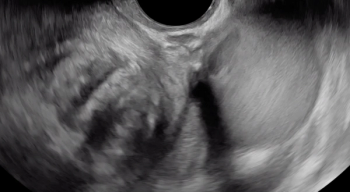

The beginning of the clip depicts a thin hyperechoic layer just deep to the vagina, which represents the rectouterine pouch peritoneum.

Following the hypoechoic layer of the bowel wall throughout the clip, viewers can appreciate the consistency of the thickness and echogenicity of this layer.